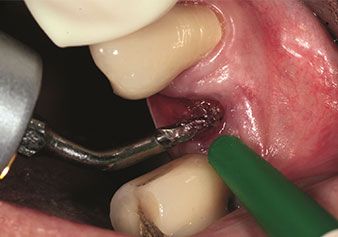

Une application souvent sous-estimée est l’extraction atraumatique de racines dentaires ou de fragments radiculaires dans le cadre d’une gestion alvéolaire. Les périotomes à denture fine, qui sont actuellement disponibles en deux versions (EX1 et EX2 de W&H), peuvent également être utilisés pour extraire facilement des dents qui ont subi un traitement endodontique spécifique préalable ou des racines ankylosées. On obtient des alvéoles d’extraction dans lesquelles à la fois les tissus durs et les tissus mous sont entièrement préservés.

Ceci instaure des conditions optimales pour un traitement implantaire ultérieur ou immédiat (Figures 1 et 2 fournies avec l'autorisation du Dr Torsten Conrad, Bingen

am Rhein).